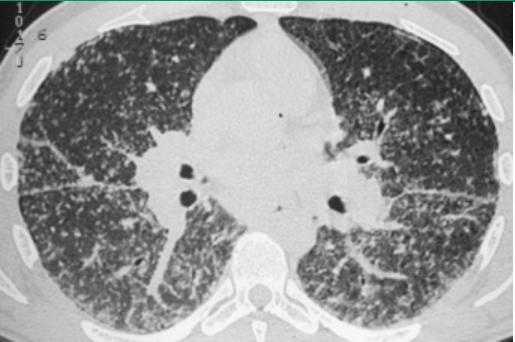

常规行胸部HRCT以评估胸片所见异常;或者评估胸片正常,但原因不明的呼吸困难或咳嗽。HRCT可发现胸部X线平片未能发现的肺实质和纵隔异常。HRCT扫描通常显示肺实质变化主要分布于中上肺野:

- 肺门和纵隔淋巴结肿大

- 支气管血管束串珠样增厚或不规则增厚

- 沿支气管、血管及胸膜下区域分布的结节

- 支气管壁增厚

- 磨玻璃样不透明影

- 肺实质肿块或结节性实变,偶伴有空洞

- 肺实质条索

- 囊腔

- 纤维化伴肺结构变形和牵引性支气管扩张

实际上HRCT检查还可以协助医生与其他疾病鉴别。

结节病,多发结节,直径1-2毫米,位于细支气管周围。主要裂隙的串珠是淋巴受累的特征。双侧门淋巴结肿大